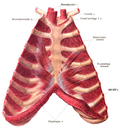

Media in category "Muscles of the human torso"

The following 90 files are in this category, out of 90 total.